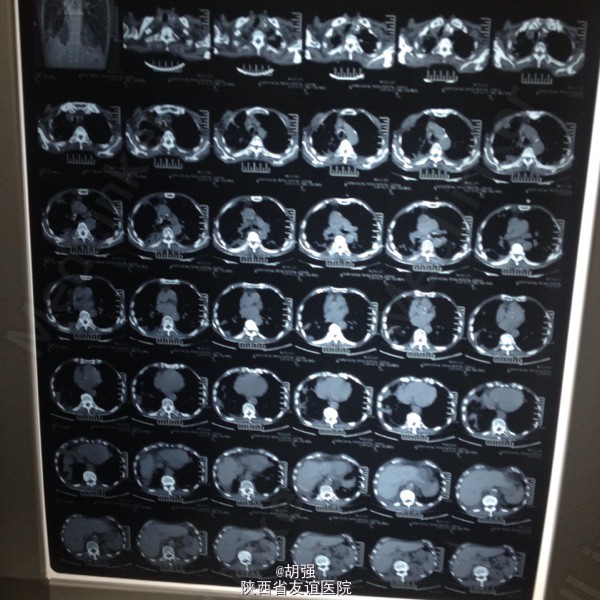

老年男性患者七十六岁。 主诉:反复咳嗽、咳痰10年,加重2月。 现病史:患者10年前受凉后出现咳嗽、咳痰,于当地医院给抗感染治疗后症状消失。此后每遇劳累或者季节交替时,反复出现咳嗽、咳痰、胸闷、气短,且逐年加重,多次住院,行胸部CT、肺功能、血气分析等相关检查,诊断为:慢性阻塞性肺疾病急性加重期,给于抗感染、平喘治疗后均能缓解(具体用药及剂量不详)。2月前受凉后,咳嗽、咳痰、气短症状加重,咳大量白色黏痰,于外院抗感染对症治疗效果不佳,遂来我院。 既往有甲状腺功能亢进病史8年,继发心房纤颤,行I131治疗;有腔隙性脑梗死病史5年。

查体:口唇略紫绀,口腔黏膜无充血、糜烂、溃疡;颈静脉怒张,桶状胸,两侧呼吸动度及语颤减弱,叩诊呈过清音,两肺呼吸音粗糙,可闻及哮鸣音及湿性啰音。心率110次/分,律不齐,心音强弱不等,各瓣膜听诊区未闻及病理性杂音。腹平软,无压痛,肝脾肋下未及,双下肢水肿。 血常规: 白细胞14.01XE9/L、中性细胞比率91%、血红蛋白170g/L、血小板370X10E9/L。

慢性阻塞性肺疾病急性加重期,肺结核?肺真菌病?支气管扩张?慢性肺源性心脏病,心功能IV级,甲状腺功能亢进症,I131治疗后,心房纤颤,脑梗死。 外院给予特治星及氟康唑治疗效果不佳。入院后给予舒普深3.0静注2次/日联合莫西沙星片o.4口服1次/日,多索茶碱0.2十甲泼尼龙20mg2次/日,镁极化液250ml十异舒吉20mg静点,酚妥拉明10mg静点及强心、利尿治疗后好转。

复查血常规正常,血气分析提示:低氧血症,代射性碱中毒,电解质示:钾低。考虑:代谢性碱中毒由低钾所致。